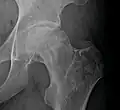

Head of the femur showing a flap of cartilage due to avascular necrosis (osteochondritis dissecans). Specimen removed during total hip replacement surgery.